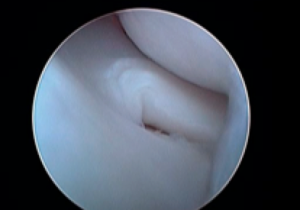

半月板の関節鏡評価

(左上)正常半月板 (右上)半月板損傷 バケツの取っ手型損傷 典型的な犬の半月板損傷の形態 (左下)半月板損傷 フラップ型 (右下)半月板損傷部を検査棒で引き出しているところ